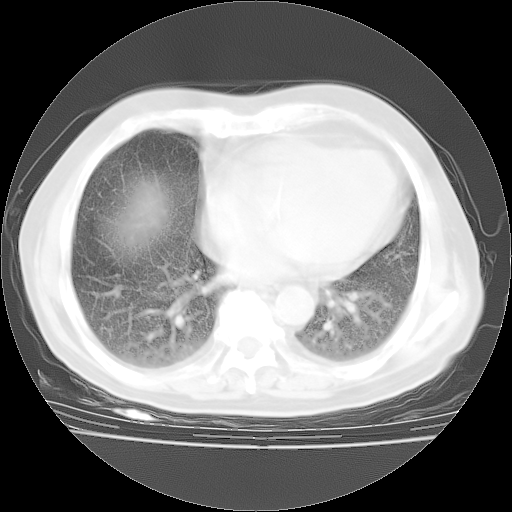

4月28日肺部CT——再次出现类似去年5月9日——透光度降低,“间质性”改变。

4月28日肺部CT——再次出现类似去年5月9日——磨玻璃样、间有“粟粒样”改变。

4月28日肺部CT

个人阅读4.14日肺部CT平扫:纵隔窗无异常,但肺窗示:双下肺内、后基底段有片絮状侵润影,部位以后基底段为著,以间质改变为主,呈急性肺泡炎征像,和首次住院影像学有相似之处。仅是个人读片,明日请相关专家再读片哈。其它建议同上。

1、108#的是4月14日的胸部CT(发此贴时还没看着28日的CT)。14日的胸部CT其实已经出现改变(如108#所述),个人认为28日的胸部CT除纵膈窗疑似有双侧胸膜增厚或少量胸积液(可行胸部B超明确)外,与4月14日对照病变有所加重;2、已经给予“异烟肼、利福平、乙胺丁醇”抗痨治疗?如果是,甲强龙80mg可缓慢减量;如果环磷酰胺已停用,暂不使用;3、中性粒细胞92%,明显升高,目前体温情况?注意合并细菌感染可能,使用左氧氟沙星情况下,是否联用B-内酰胺类抗菌药物?另外是查免疫全套非风湿全套。

今请临免主任会诊后认为:4月14日胸部CT已有双下肺间质性改变。患者病情复发多系激素减量过快不正规所致。目前甲强龙80mg/日,一周后酌情开始减量,不易过快。环磷酰胺若已停用,暂不使用。他同意目前抗菌药物使用,但应考虑是否加用B-内酰胺类抗菌药物(中性细胞明显增高);2、结核复发目前依据不足;3、若免疫全套各项指标正常,考虑多系特发性肺间质炎可能大。4、加强支持,并注意保护胃黏膜。